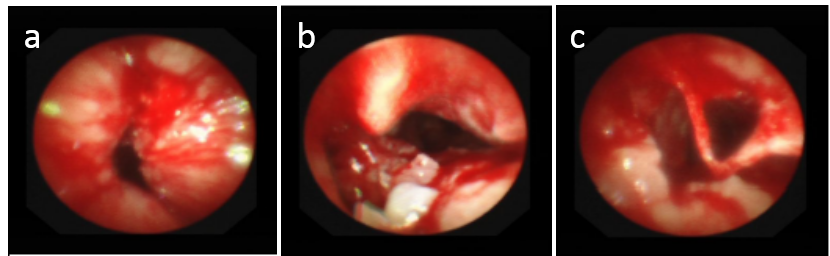

电子支气管镜检查显示气管上段新生物

因为上段气道狭窄,无法运用常规气管插管呼吸支持,麻醉科主治医师武昊天采用喉罩气管插管建立麻醉下机械通气。牟向东在气管镜下应用Nd:YAG激光,由近及远逐渐烧灼消融气管内肿瘤,间断应用“氩气刀”(APC)止血治疗。在应用冷冻探头清除气道内的坏死物后,气管管腔逐渐扩大。之后牟向东经支气管镜置入气管内导丝并沿导丝放入气管支架,应用活检钳调整支架到合适位置。“放置后,气管支架受到肿瘤组织压迫变形,我们使用气管球囊在支架内进行扩张,支架完全张开后,气管管腔完全恢复通畅。”牟向东说。术后刘先生的喘憋症状得到了明显缓解,近日已康复出院。